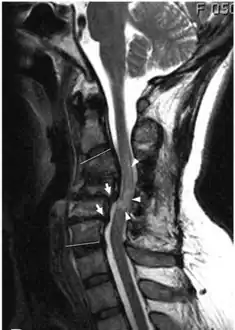

MRI shows retrolisthesis arrows ( and signal change at C3-C5 arrow heads)

Retrolisthesis of L5-S1